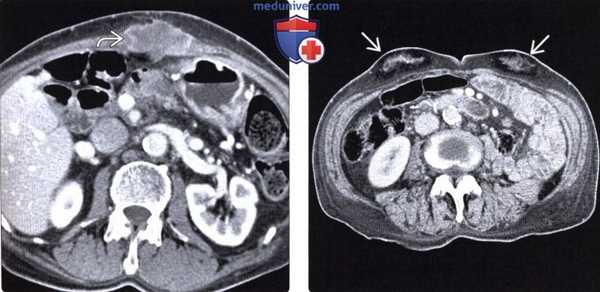

(Слева) На аксиальной КТ с контрастным усилением у пациента после операции Уиппла, выполненной при раке поджелудочной железы, определяется неправильной формы гиподенсное объемное образование, возникшее в области разреза брюшной стенки, идентифицированное на операции как рецидивная опухоль.

(Справа) Диабетическая липогипертрофия у пожилого мужчины: визуализируются образования состоящие из жировой и фиброзной ткани, располагающиеся с обеих сторон в подкожной клетчатке в околопупочной области. Этот пациент получал инъекции инсулина в одни и те же области брюшной стенки в течение многих месяцев.